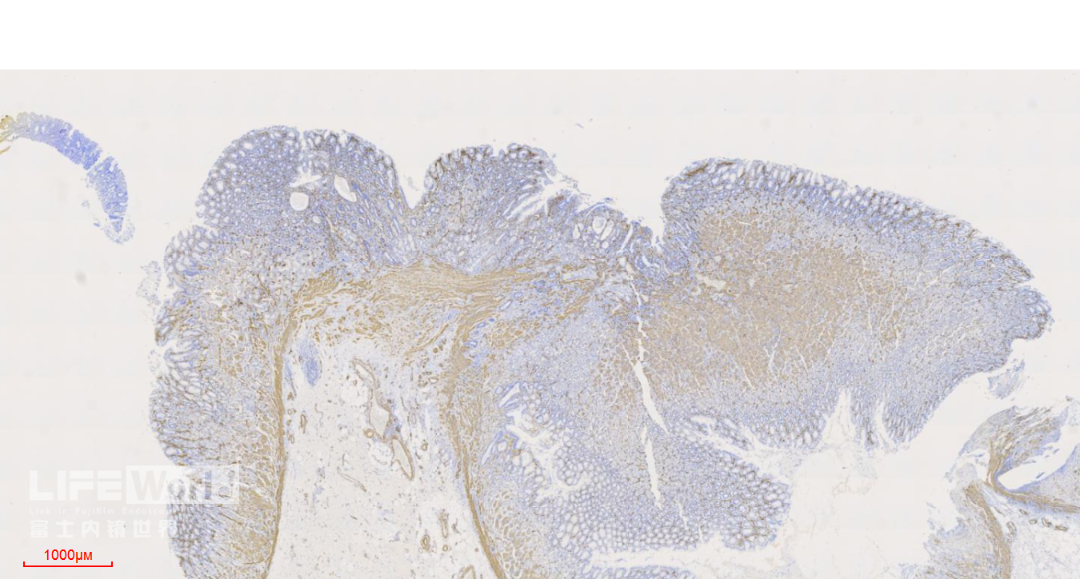

HE染色:2号切片示中分化腺癌,6号切片示高级别上皮内瘤变,局灶癌变。

这是2号切片,病变位于一条皱襞顶端。

病变处(红圈内)可见不规则的腺管状结构,部分呈筛网状。图中可以看出,病灶间可见相对正常的胃底腺结构。图片中最深的病灶已经侵及粘膜肌层。

此为病变最深的地方,癌变的腺管侵及粘膜肌层。

CK-pan染色显示肿瘤细胞为上皮细胞,呈不规则腺管状排列,提示为中分化腺癌。

SMA染色:粘膜肌层完整,肿瘤细胞侵及粘膜肌层,但未突破。